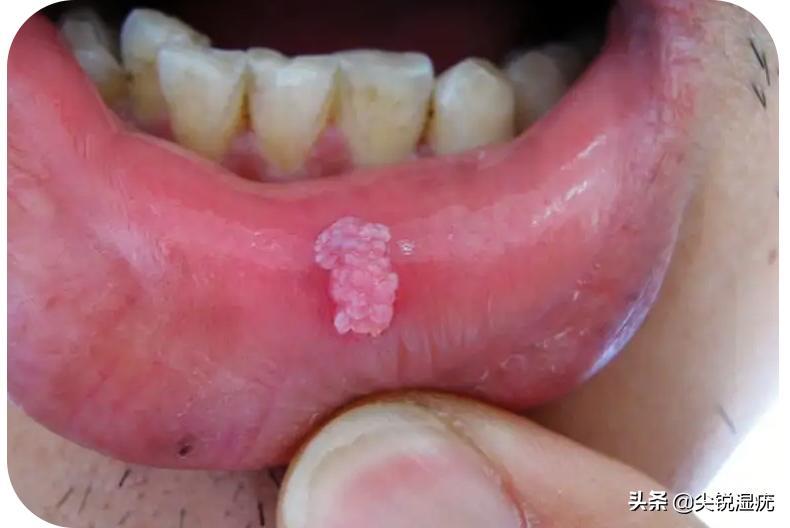

口腔尖锐湿疣与其他部位的尖锐湿疣一样,其实都是同一种疾病,只是发生的部位在口腔而已。该病是由于局部鳞状上皮感染了人乳头瘤病毒(HPV)而引起的性传播疾病,它发生在口腔这个部位比较少见,大多数感染者还是以外阴生殖器及肛周部位感染为主。可能不少人会好奇地问一句,为什么说口腔尖锐湿疣比较少见呢?其实,正常人口腔很难长尖锐湿疣的,具体缘由我们往下接着看。

尖锐湿疣是性传播疾病的一种,即便是发生在口腔部位也仍然如此。也就是说,口腔这个部位感染尖锐湿疣主要原因也是因为不洁性接触导致的,而这个部位的不洁性接触指的就是口腔性行为。那么,如果一个人没有任何口腔性行为或者没有不洁的性接触史,他们感染上尖锐湿疣的风险是非常低的。而口腔这个部位感染的可能性就更低了。因为口腔中含有溶菌酶,对外来的病毒、细菌等都有抑制作用,何况没有不洁性史的人很难接触到HPV病毒,也就不容易发生在口腔这个部位。所以说,口腔这个部位的确不容易感染尖锐湿疣。

如果不小心确诊口腔部位感染上了尖锐湿疣,建议要同时检查下自己的外阴生殖器及肛周等易感区域是否也已经感染发病。如果多个部位患病的,是需要同时接受治疗的,否则一个部位治疗好,另一个部位还未治疗,还可能再次交叉感染,导致伴侣发病或者自体接种传染引起的其他部位长出疣体。由于口腔这个部位比较敏感,在具体治疗上要选择温和无痛,标本兼治的方法更为有效,也不至于造成较大创面,让患者难以坚持治疗。相比之下,通过中医中药组方口服外用是能让人接受的,也可以使其康复。